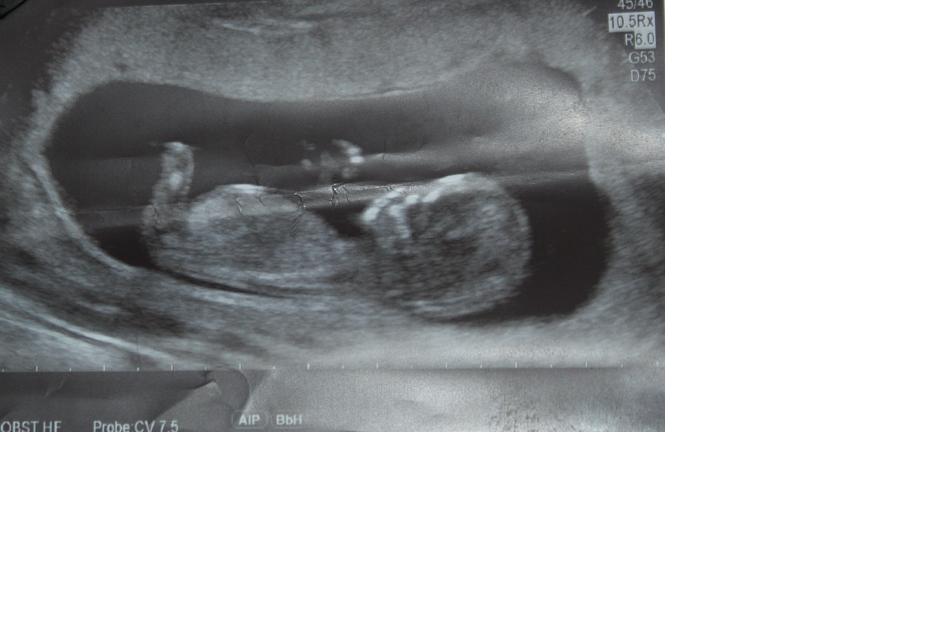

This is my 12 week scan, made last week during CVS.

I'm sorry for the very irritating paper fold right over the baby. It reflects badly on the camera, couldn't get rid of it...

Do you see a nub? (I don't)

What do you think of the skull? (if you can see it because the paper fol might be in the way)